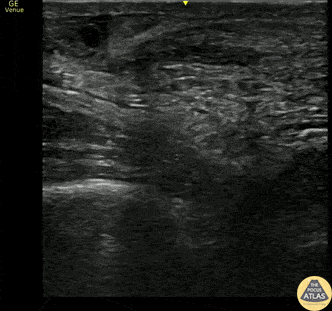

20s M presented with calf/heel pain after skateboarding, found to have a positive Thompson test. POCUS confirmed a full thickness tear of the achilles tendon. The patient was splinted and referred to orthopedic surgery for repair. Alexandrea Netto PA, Denver Health and Hospital Authority Lois Isaksen MD, Attending Physician, Denver Health Residency in Emergency Medicine